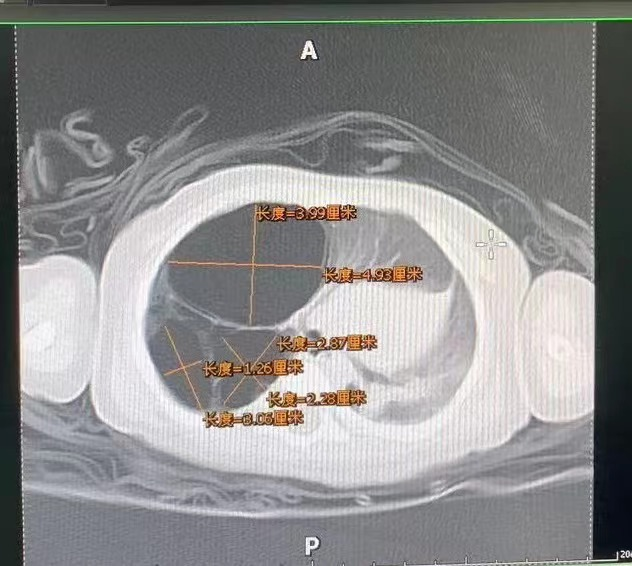

小小出生后最初沒有明顯癥狀,近期,她突然咳嗽咳痰加劇,吸氣困難口唇青紫在當(dāng)?shù)蒯t(yī)院檢查肺部CT發(fā)現(xiàn)右肺3個(gè)囊性病灶有最大的3.99×4.93×4.6cm,相當(dāng)于一個(gè)雞蛋大小。